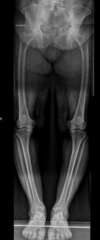

Arthrose interne du genou sur déformation du squelette en genu varum /

Traitement chirurgical côté gauche dans un premier temps par ré-axation grâce à une ostéotomie tibiale de valgisation